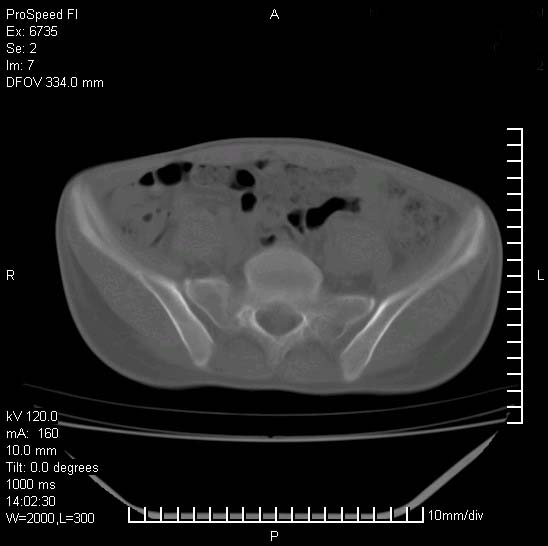

患者自诉胯部疼痛两年余,在当地服用中药,半月前至本院考虑骶髂关节结核,给予抗痨治疗。现发展至右下肢疼痛明显,活动受限,以膝关节处明显,拍膝关节平片无明显异常。

两侧骶骼关节改变,考虑强直性脊炎

左侧骶髂关节面限局性骨破坏,边缘硬化关节腔见钙化物;不出外tb

右侧骶髂关节也有类似改变,只是较左侧轻,首先考虑强直性脊柱炎,不除外结核,建议作hla-b27检查。

典型强脊炎改变,髋关节亦有累及

符合强直性脊柱炎表现。